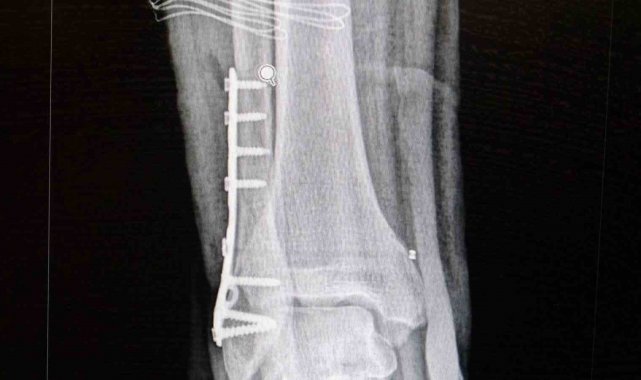

Ortopedi polikliniklerine en sık ayak bileği, diz ve omuz yaralanmalarıyla başvurulduğunu belirten Demirbaş, futbol nedeniyle yaralanma oranlarının da ilk sırada yer aldığını söyledi. Konuya ilişkin Demirbaş, "Futbolda menisküs yırtıkları, ön çapraz bağ yırtıkları, iç ve dış yan bağ yaralanmaları, aşil tendon kopmaları ve ayak bileği bağ yaralanmaları çok sık görülüyor. Ayrıca spora bağlı kırıklar da önemli bir yer tutuyor" ifadelerini kullandı.